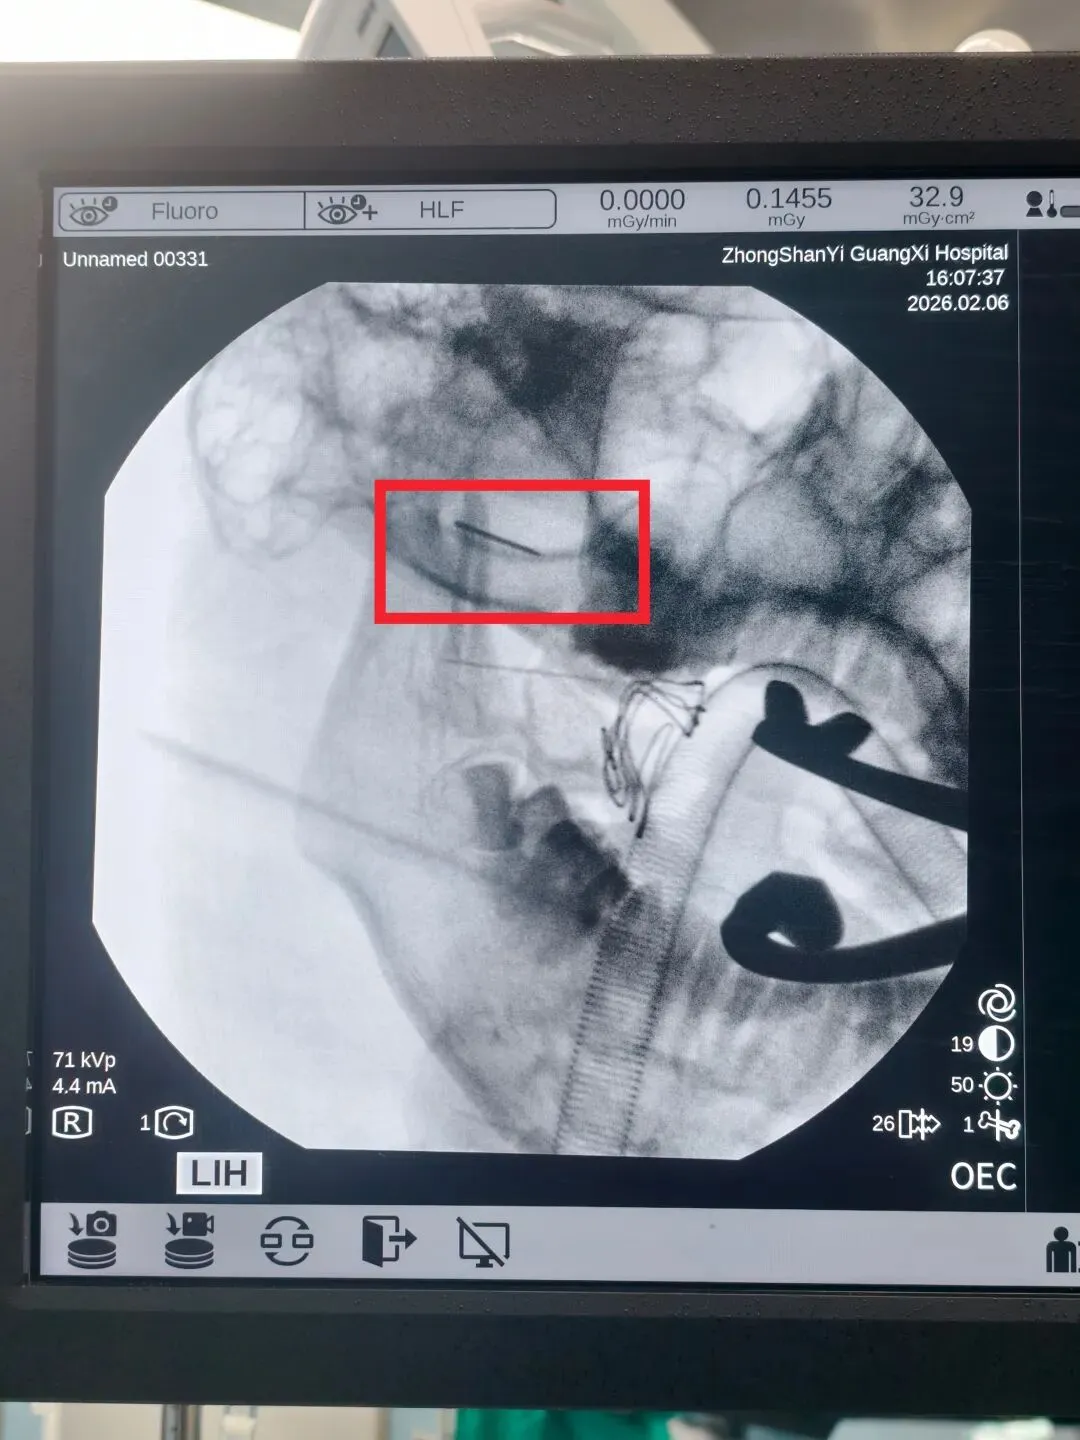

最终,团队为该男孩制定了个性化治疗方案,在气管插管全麻下,借助移动C臂X射线机多角度定位,为了防止断针跟随面部的软组织移动,团队使用高强度磁铁将断针固定,花了30分钟,经口实施手术成功取出断针。耳鼻咽喉头颈外科主任医师唐亮介绍:“这个针取出来,我们测量了一下大概是1.6厘米的长度。”